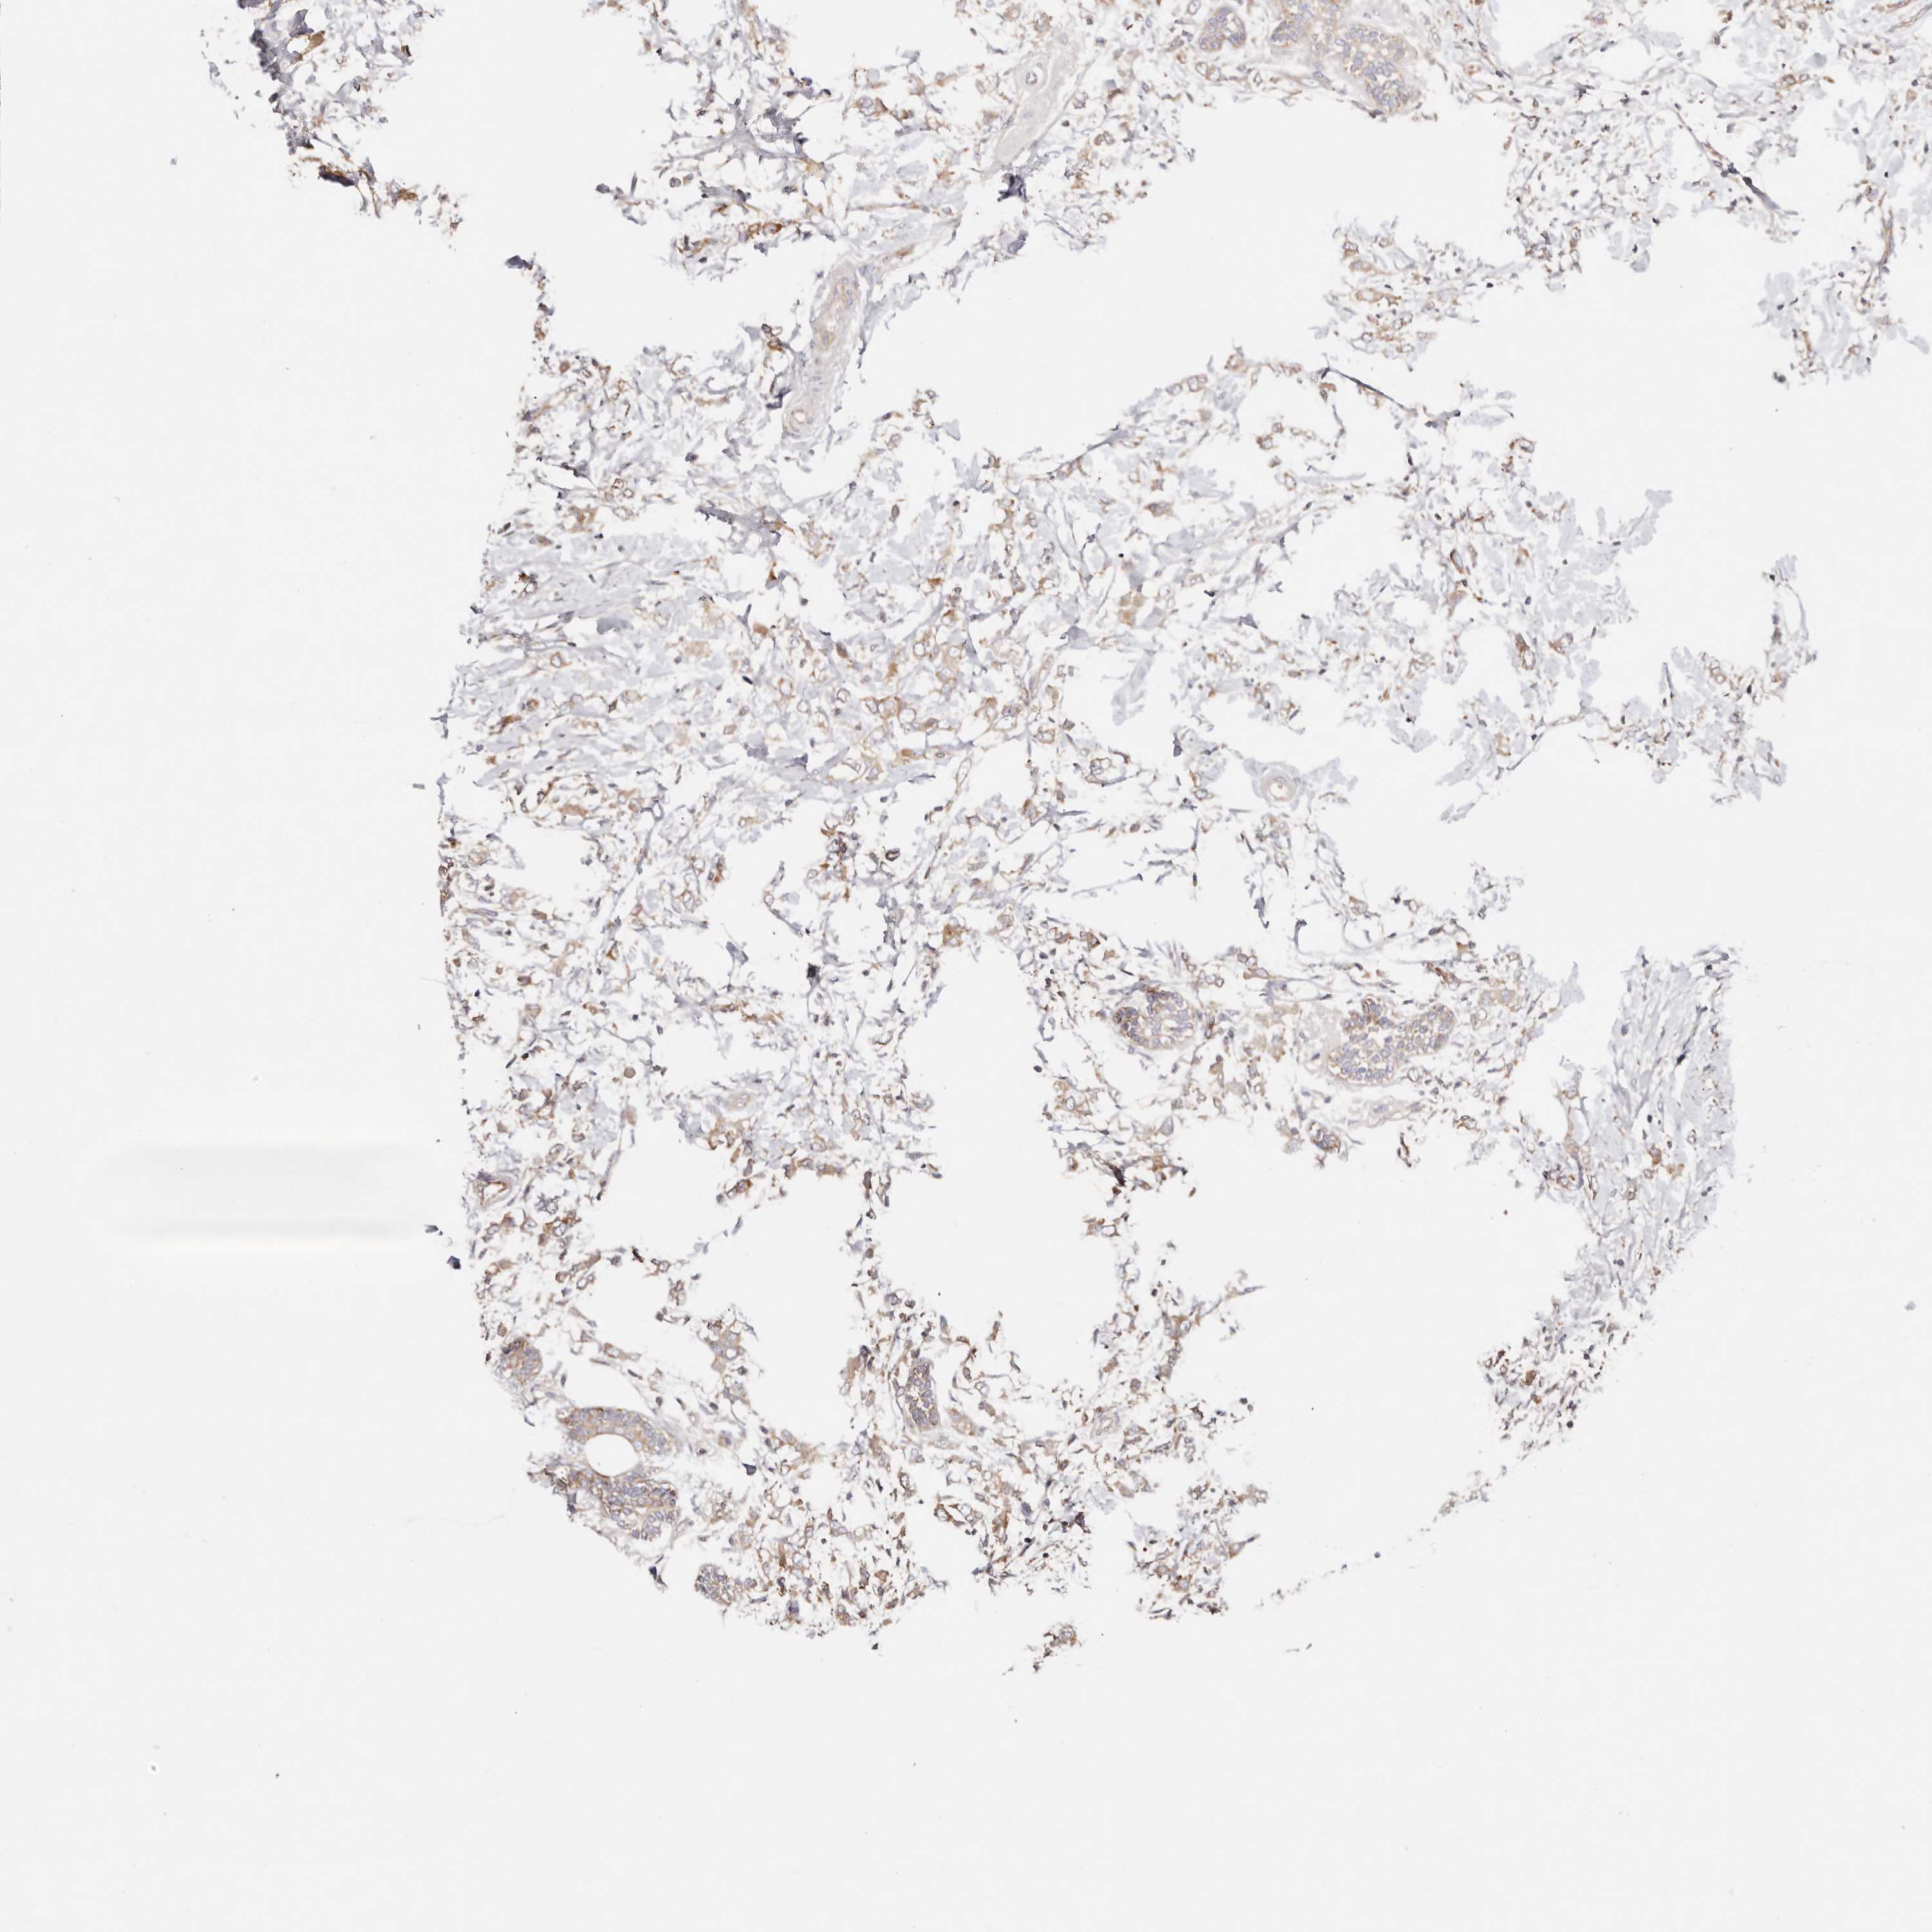

Breast cancer

Human cancer